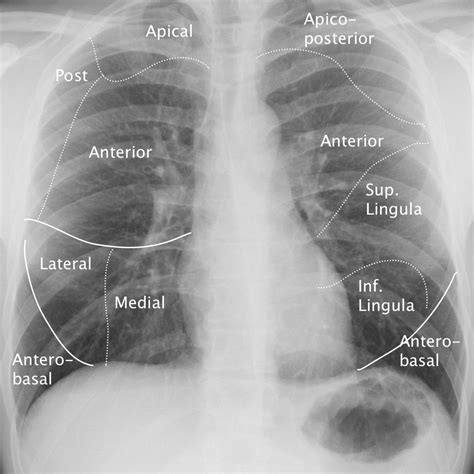

The term "lingula" is derived from the Latin word meaning "little tongue," which accurately describes its appearance as it extends downward and forward from the left upper lobe of the lung. It is the anatomical equivalent of the middle lobe found in the right lung. Positioned adjacent to the cardiac notch—the indentation where the heart rests against the lung—the Lingula of left lung effectively wraps around the lateral aspect of the heart.

Structurally, the lingula is divided into two distinct bronchopulmonary segments: the superior lingular segment and the inferior lingular segment. These segments receive oxygenated air through the lingular bronchus, a branch of the left upper lobe bronchus. Because of its location in the lower portion of the upper lobe, it is often a site of specific pathological interest, particularly regarding aspiration and infection.

Medical imaging, such as a chest X-ray or CT scan, often highlights the lingula during the diagnostic process. Infiltrates located in this area may cause a "silhouette sign," where the borders of the heart become obscured on a frontal chest radiograph because the lung density matches the heart's density. Recognizing this is vital for clinicians to distinguish between lingular pneumonia and left lower lobe pathology.